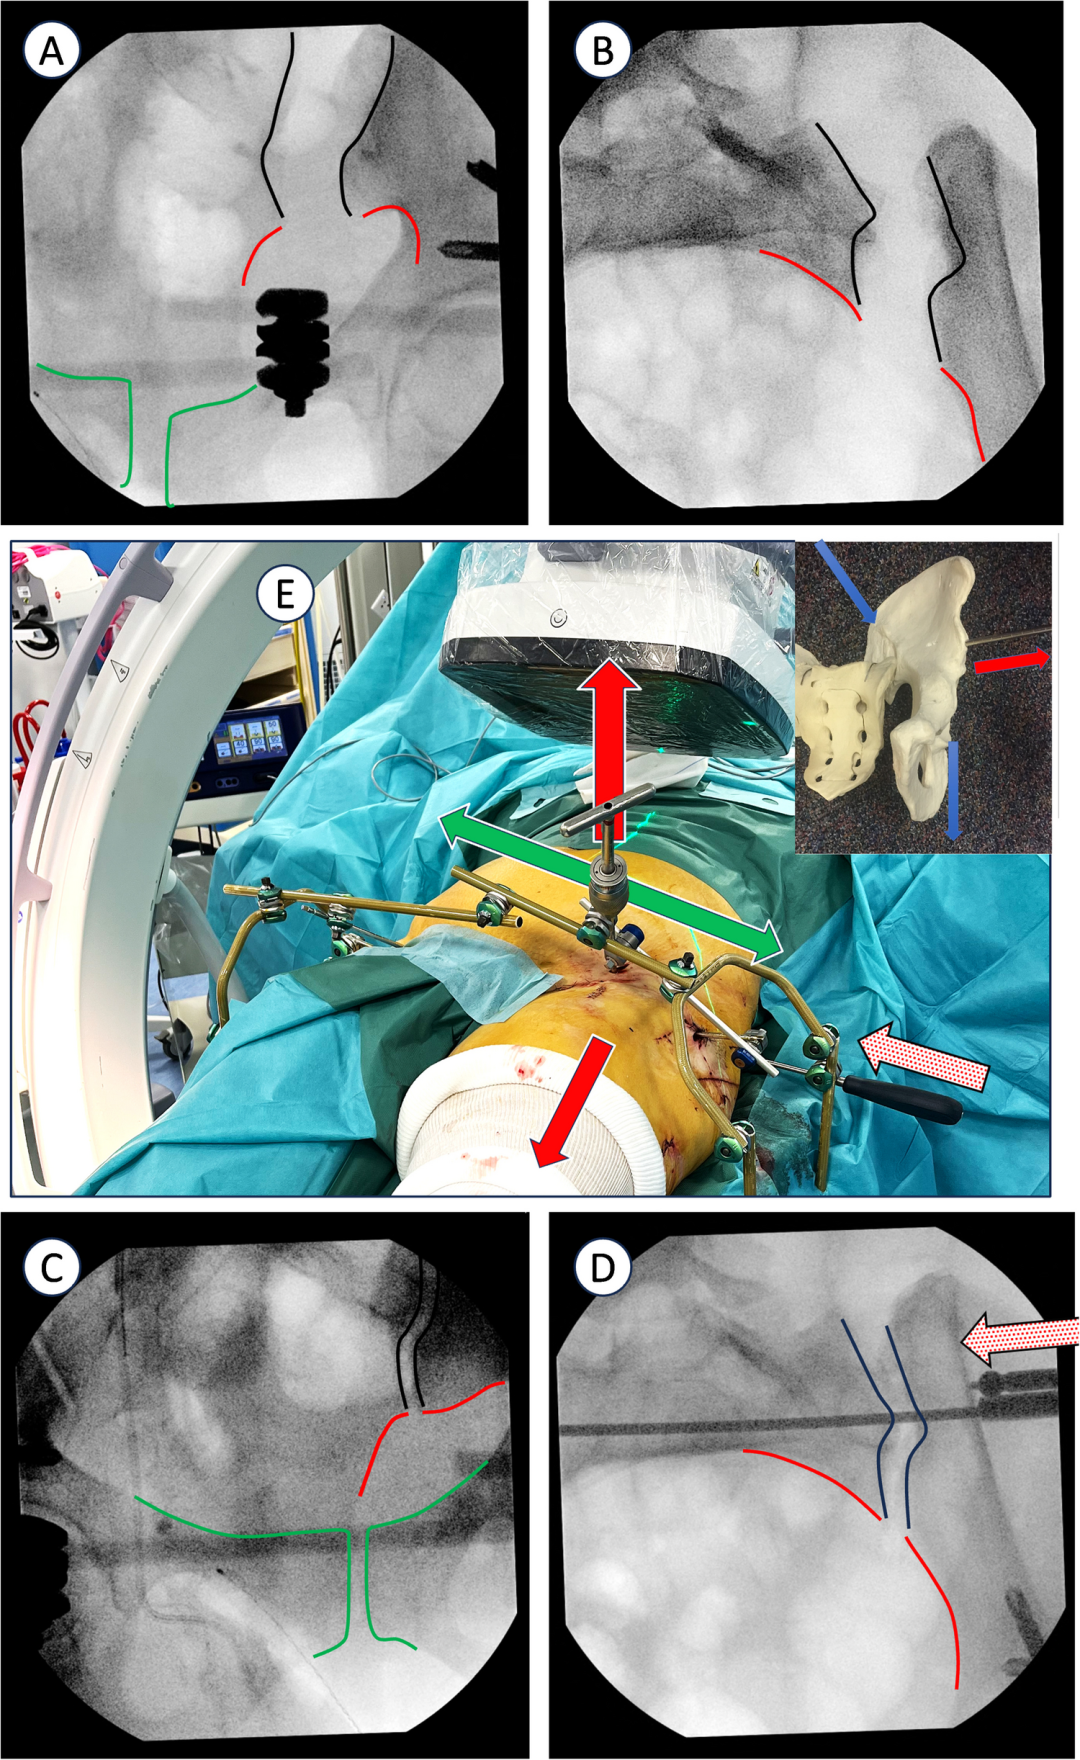

2、外固定器置入 :第一阶段是在两侧无名骨(受伤侧和未受伤侧)置入固定针。每个半骨盆采用双正交固定:额状面的髋臼上针和矢状面的 LC2 通道针。(图1a - 1b)此技术可增强头侧 / 尾侧复位控制并提高旋转稳定性。固定针设置如下:在标准前后位(AP)视图下,将额状面的髋臼上针置于髋臼眉弓上方,直达无名骨内板且避免损伤关节。对于 LC2 针,可用泪滴视图或 "Teepee" 视图(出口闭孔位)观察通道,但由于器械操作干扰,不一定需获取该视图。因针长及透视下对准通道轴有难度,故采用两个正交视图。髂骨视图用于确定髂前下棘(AIIS)的进针点,并引导头尾轨迹,目标是坐骨大切迹头侧。入口闭孔视图则确保针不置于盆内或盆外。

然后围绕患者组装固定架。图 1 展示了最全面的设置版本,依损伤情况也可选用更轻便版本。用横杆连接系统左右部分以增强稳定性,将骨盆未受伤侧 “锁定” 到相邻支架部分,以便更有效地操纵受伤侧。需识别关键放射学标志,入口位视图中包括耻骨联合前部和后部、骶髂关节前部(一侧坐骨支撑内板和另一侧骶骨翼)、骶椎前壁;出口位视图中包含耻骨联合(耻骨上支)、坐骨大切迹及其与骶骨形成的曲线、骶髂关节头侧部分和髂嵴。除标准入口位和出口位视图外,入口闭孔视图(“沿骶髂关节视图”)能清晰显示骶髂关节和髂结节外板,利于更精确控制髂骶骨(IS)或经骶骨(TS)螺钉的放置和长度。(图2)

图2:使用支架构建技术纠正宽大骶髂关节的病例示例,以闭合骶髂关节分离

3、复位操作 :为实现头侧移位,通常需轴向牵引,此时在LC2针上置T型手柄,有助于调控受伤骨盆的前后平移与旋转(常见畸形为半骨盆相对完整骶骨外旋且后移)。而额状面的髋臼上针则用于调控受伤骨盆的内翻/外翻对线。当某一参数复位满意后,便将相应针固定于支架上,以便继续完成其他复位操作直至整体复位满意。例如,球头推杆可用于闭合骶髂关节分离(图2)。若后侧平移仍存在,可将Schanz针悬吊固定于支架柱上,借助患者体重或重力逐步纠正后侧半平移。